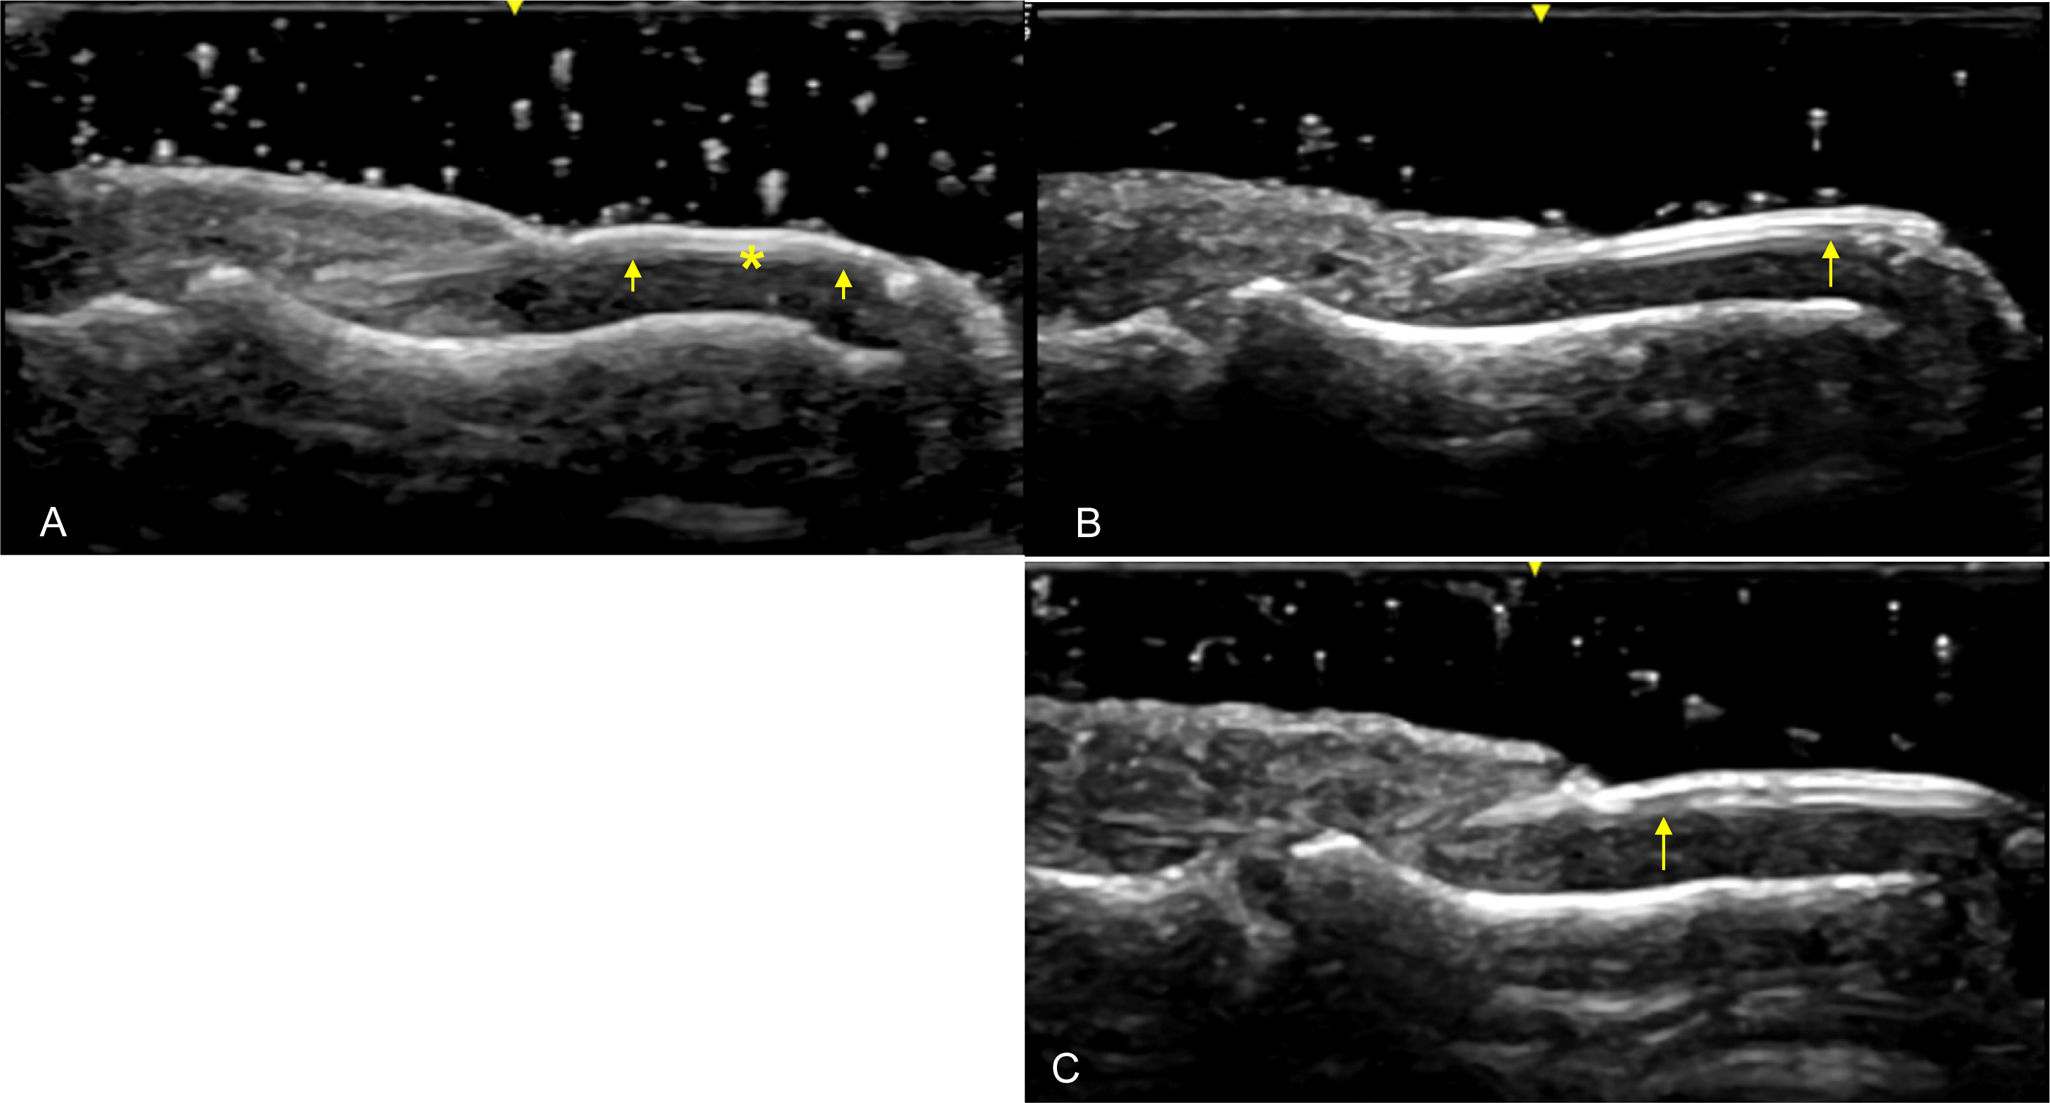

Ultrasound imaging identifies three primary structures of the nail apparatus: the nail plate, the nail bed, and the nail matrix. The nail plate consists of two parallel hyperechoic layers, separated by a hypoechoic interlaminar space, with normal thickness ranging between 0.3 and 0.65mm. The nail bed, a hypoechoic structure located between the ventral plate and the periosteum of the distal phalanx, measures between 0.7 and 6.5mm in thickness. The nail matrix, located proximally, appears isoechogenic and measures 1–5.3mm in length [134] (Fig. 5).

Fig. 5.Healthy Nail (Longitudinal View): Sonographic image obtained using Logiq e US system with an 8–18i MHz linear transducer. The nail plates (np) appear as two parallel hyperechoic layers, separated by a hypoechoic interlaminar space. The nail matrix (nm) is visible as an isoechogenic structure located proximally, while the nail bed (nb) is shown as a hypoechoic area between the ventral nail plate and the periosteum of the distal phalanx (dp). The extensor tendon (et) inserts distally at the base of the dp. mp=middle phalanx.

Ultrasonographic studies in psoriatic disease have shown significant increases in the thickness of the nail plate, bed, and matrix compared to healthy individuals, as well as compared to those with rheumatoid arthritis (RA) or osteoarthritis (OA). These alterations are present even in subclinical stages, highlighting its utility as a tool for early diagnosis and differential assessments in psoriatic nail disease [135,136].

Ultrasound is especially useful for detecting early psoriatic nail changes, such as minimal thickening of the nail bed or slight loosening of the ventral plate (Fig. 6). As the disease progresses, more pronounced alterations occur, including thickening of both the ventral and dorsal nail plates. In these advanced stages, the trilaminar structure of the nail plate, characteristic of healthy nails, is completely lost. The nail plate becomes thickened, wavy, and hyperechoic, with an inhomogeneous appearance [133,137] (Fig. 7). Power Doppler (PD) is particularly valuable for assessing inflammation in the nail matrix and bed, grading vascularization on a scale from 0 to 3, where higher values indicate greater inflammation [20].